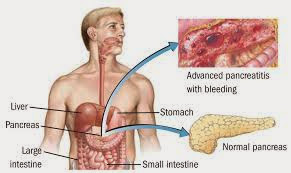

Η Παγκρεατίτιδα είναι οξεία ή χρόνια φλεγμονή του παγκρέατος. Τα οξέα επεισόδια τις περισσότερες φορές χαρακτηρίζονται από ισχυρό κοιλιακό άλγος, που ακτινοβολεί από το πάνω μέρος της κοιλίας ως την πλάτη και μπορεί να προκαλέσουν από μετρίου βαθμού διόγκωση του παγκρέατος ως δυνητικά θανατηφόρα παγκρεατική ανεπάρκεια.

Η οξεία παγκρεατίτιδα είναι μια κατάσταση αυτοπεψίας του αδένα και ενδεχομένως, των παρακείμενων οργάνων. Μπορεί να περιπλέκεται με νέκρωση, μόλυνση και ανεπάρκεια άλλων οργάνων. Το ποσοστό θνησιμότητας είναι 5 έως 10%.

Σε φυσιολογικές συνθήκες τα πεπτικά ένζυμα είναι αδρανή και ενεργοποιούνται μόνο για την πέψη των τροφών όταν φθάσουν στο λεπτό έντερο. Σε περίπτωση όμως που το πάγκρεας φλεγμαίνει, ενεργοποιούνται ενώ βρίσκονται ακόμη μέσα σε αυτό και του «επιτίθενται», καταστρέφοντας το. Η κατάσταση αυτή μπορεί να είναι οξεία ή χρόνια.

Ξεχωρίζουμε την οιδηματώδη οξεία παγκρεατίτιδα (το οίδημα επηρεάζει μόνο το πάγκρεας), με συνήθως ήπια εξέλιξη και την αιμορραγική-νεκρωτική οξεία παγκρεατίτιδα πιο σπάνια, αλλά μπορεί να είναι και θανατηφόρος. Η δεύτερη χαρακτηρίζεται από νέκρωση του συνόλου ή μέρους του παγκρέατος και από εξιδρώματα εκτός από την φλεγμονή του παγκρέατος. Ο κίνδυνος που υπάρχει είναι η μόλυνση της νέκρωσης που είναι η κύρια αιτία θνησιμότητας.